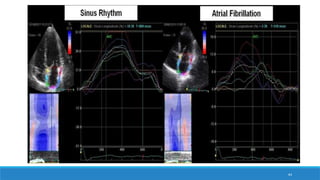

Etude de l’OG

Etude fonctionnelle:

-Méthode des volumes (écho 2D, 3D)

-la méthode du Doppler spectral mitral et du flux veineux pulmonaire

-l’analyse de la déformation myocardique atrial ou le strain atrial (2D speckle tracking).

→ Intérêt pronostique

STRAIN OG

 Une fonction «réservoir» n responsable d’un strain(S) et strain rate (SR) secondaire à l’étirement des fibres

atriales gauches lors du remplissage de l’OG.

 Une fonction «conduit» v responsable d’un strain et strain rate secondaire au raccourcissement des fibres

atriales gauches lors de la vidange de l’OG en proto et mésodiastole.

 Une fonction «pompe» correspondant à la contraction atriale avec un raccourcissement actif des fibres

myocardiques atriales gauches responsable d’un S et SR négatifs.